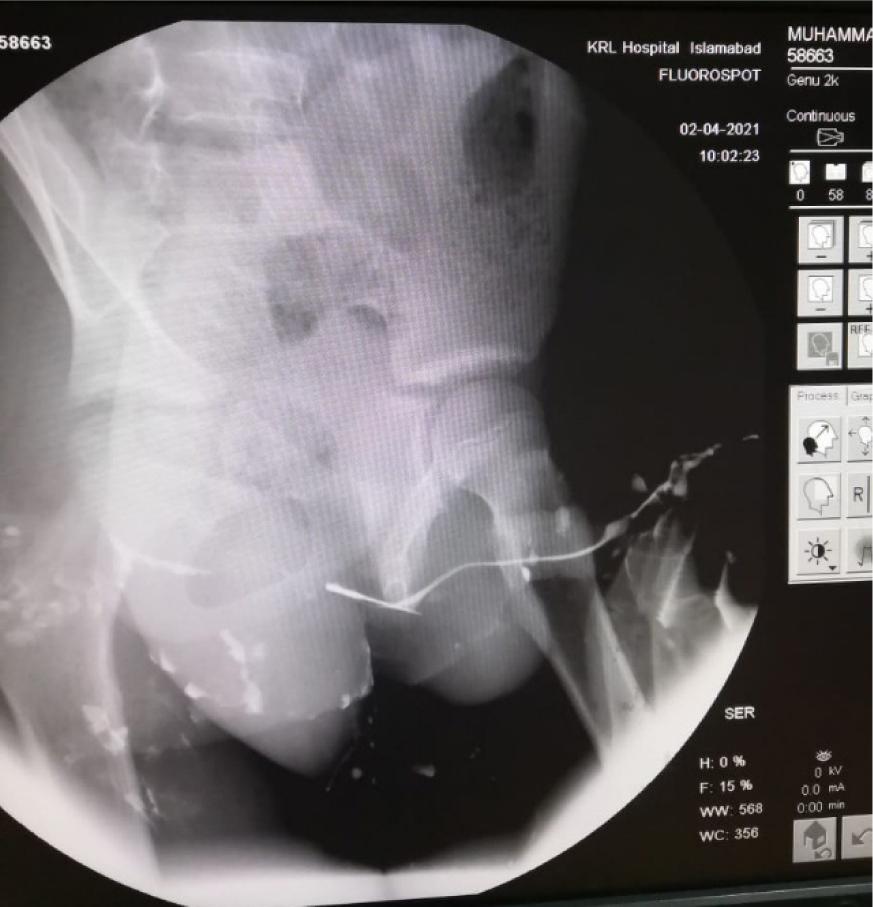

An 11-year-old boy presented in the paediatric out-patient department of KRL Hospital Islamabad with poor urine flow, weak stream, and pain in pubic region for 3 weeks. The attending physician examined the patient and upon a detailed examination, genitourinary tract stricture was suspected. The patient was referred to the department of urology. The urologist ordered retrograde urethrography (RUG) to investigate the cause of urinary retention. The RUG showed a thin sharp opaque in the urethra. A sharp needle at the posterior urethra was found along with an incidental finding that is, fracture of the inferior ramus of pubis (Figures 1 and 2). Hence, foreign body urethra was diagnosed.

Figure 1: Micturating urethrogram showing foreign body in posterior urethra.